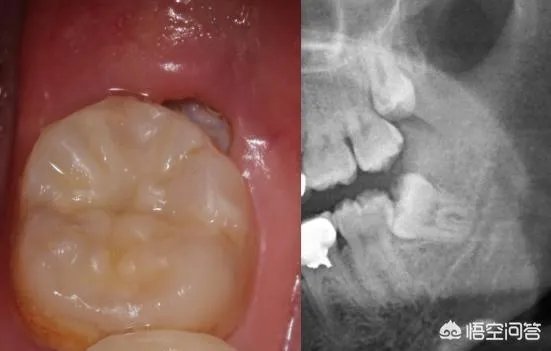

如图,智齿距离下颌骨尚有一段距离,按wuli大幂幂的说法,拔去上下两颗智齿下颌骨就能变小了?EXO me?

长歪的智齿,医学上称为阻生齿。要么完全埋伏在颌骨里,得靠拍牙片才能发现;要么“小荷才露尖尖角”,只冒出一点小牙尖。拔除阻生齿,周围的软、硬组织基本没啥变化,对瘦脸不会有丝毫作用。